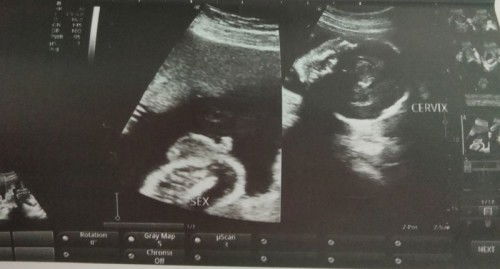

Hello po normal po ba yung ultrasound ko and confirm na po kaya na baby boy si baby ? 😊

Hindi ko pa alam kung gender niya yung nakalawit o ano basta binigay lang po sakin yung resulta hindi po pinaliwanag sakin kung ano po iyon 😂 at hindi ko rin po maintindihan, kayo po ba mga ka mommy? Yun po kaya ang gender niya? at yung isa po na picture na katabi ng head cephalic , ay legs po ba niya? #23weeks4day #firsttiimemom